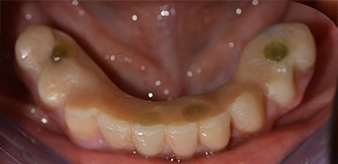

La paziente, 64 anni, presenta una dentatura residua di denti 38, 33 e 43 e una protesi combinata innestata nella mandibola (Fig. 1 e 2).